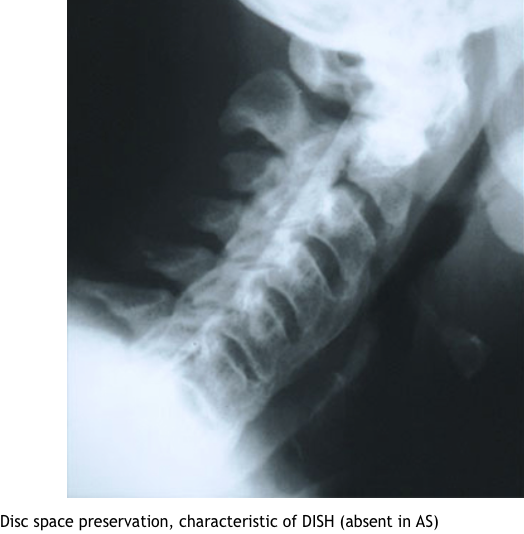

what are the radiographic findings of DISH

cf ankl spon

marginal syndesmophytes, bamboo spine, ossificiation of disc space, osteopenia, strong assoc wiht HLA b27, younger pts, bilateral sacroilitis